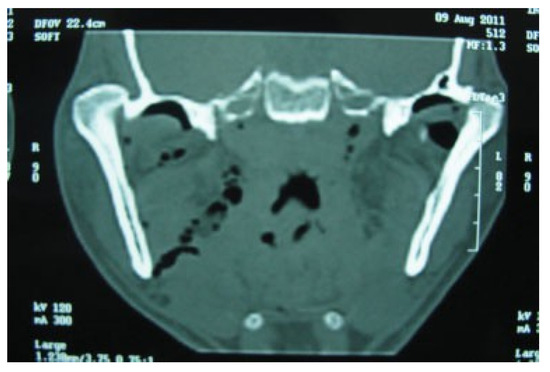

Pathologic Fractures in Bisphosphonate-Related Osteonecrosis of the Jaw—Review of the Literature and Review of Our Own Cases

Background Bisphosphonates are powerful drugs used for the management of osteoporosis and metastatic bone disease to avoid skeletal-related complications. Side effects are rare but potentially serious such as the bisphosphonate-related osteonecrosis...